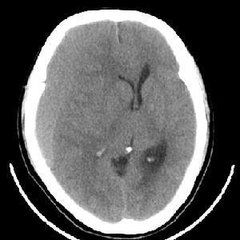

6.CT顯示等密度影較多見CSDH的CT顯示有高密度,低密度,等密度和混雜密度影4種表現,老年患者顯示等密度者較中青年多,因此,應注意腦室系統受壓和中線結構移位等現象,並進一步行MRI或腦血管造影或強化CT檢查以確診。